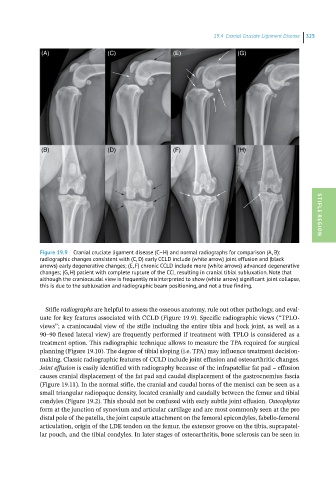

Figure 19.9 Cranial cruciate ligament disease (C–H) and normal radiographs for comparison (A, B): STIFLE REGION

radiographic changes consistent with (C, D) early CCLD include (white arrow) joint effusion and (black

arrows) early degenerative changes; (E, F) chronic CCLD include more (white arrows) advanced degenerative

changes; (G, H) patient with complete rupture of the CCL resulting in cranial tibial subluxation. Note that

although the craniocaudal view is frequently misinterpreted to show (white arrow) significant joint collapse,

this is due to the subluxation and radiographic beam positioning, and not a true finding.